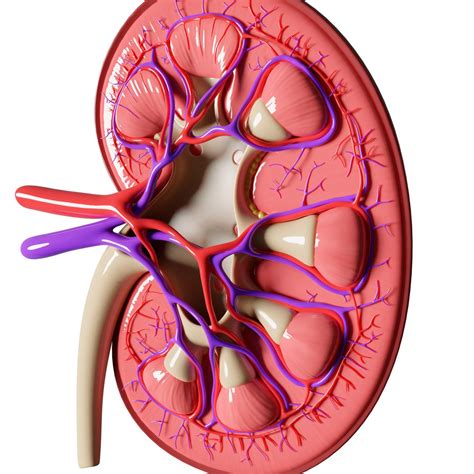

When you look at a kidney picture , you’ll typically see two bean-shaped organs, each about the size of your fist. Healthy kidneys have a smooth, reddish-brown appearance. Anatomically , they are located in the abdominal cavity, near the spine, protected by the lower ribs. The right kidney sits slightly lower than the left to accommodate the liver. In a kidney picture, you’ll notice several key components:

- Renal Capsule: This is a tough, fibrous layer that surrounds the kidney, providing protection.

- Renal Cortex: The outer region of the kidney, containing the nephrons, which are the functional units responsible for filtering blood.

- Renal Medulla: The inner region, consisting of renal pyramids that collect urine.

- Renal Pelvis: A funnel-shaped structure that collects urine and directs it to the ureter.

- Ureter: A tube that carries urine from the kidney to the bladder.

Healthy kidneys in a picture should have well-defined structures, without any signs of swelling, scarring, or other abnormalities. The blood vessels, including the renal artery and renal vein, should appear clear and unobstructed, ensuring proper blood flow to and from the kidneys. Understanding the visual characteristics of healthy kidneys is the first step in recognizing potential issues.